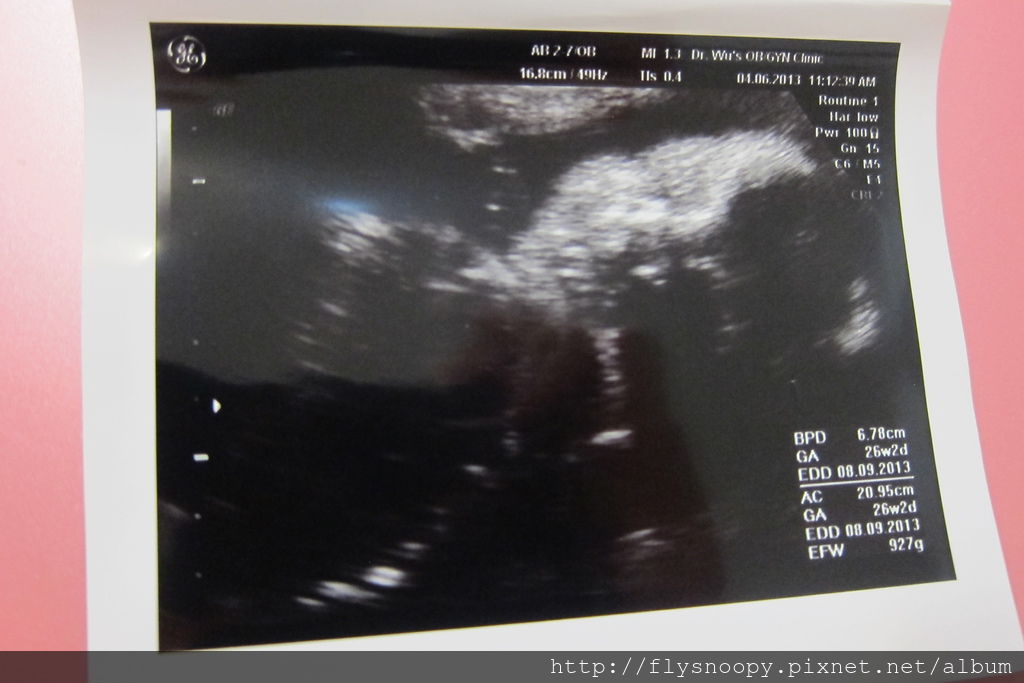

抽完血就照音波,但是這次的照片都滿不清楚的

EFW:927g

這次樂樂胎位轉正了,但是有臍帶繞頸的現象